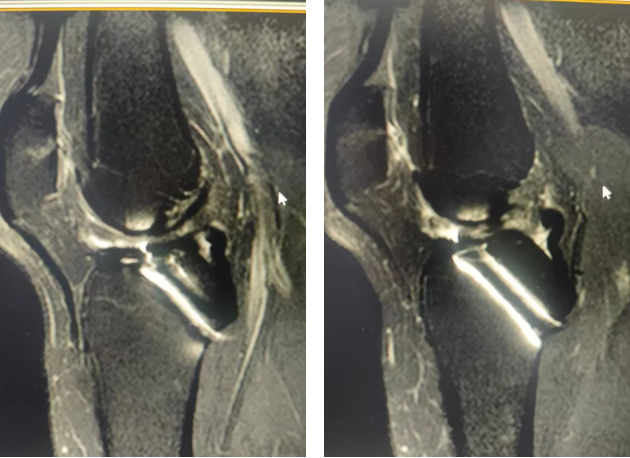

术前膝关节MRI检查

45岁的朱女士被膝盖不稳折磨了15年,近两个月更是频繁出现关节交锁。当多家医院因内固定取出难度高而拒绝手术时,朱女士经多方打听来到郑州大学五附院骨科一病区,找到徐明杰主任就医。徐明杰主任与张鹏飞医师为其查体后发现患者抽屉试验阳性,考虑患者膝关节不适不仅和内固定有关,而且可能和交叉韧带损伤有关,复查MRI检查后果然发现前交叉韧带断裂。

术后复查膝关节MRI检查